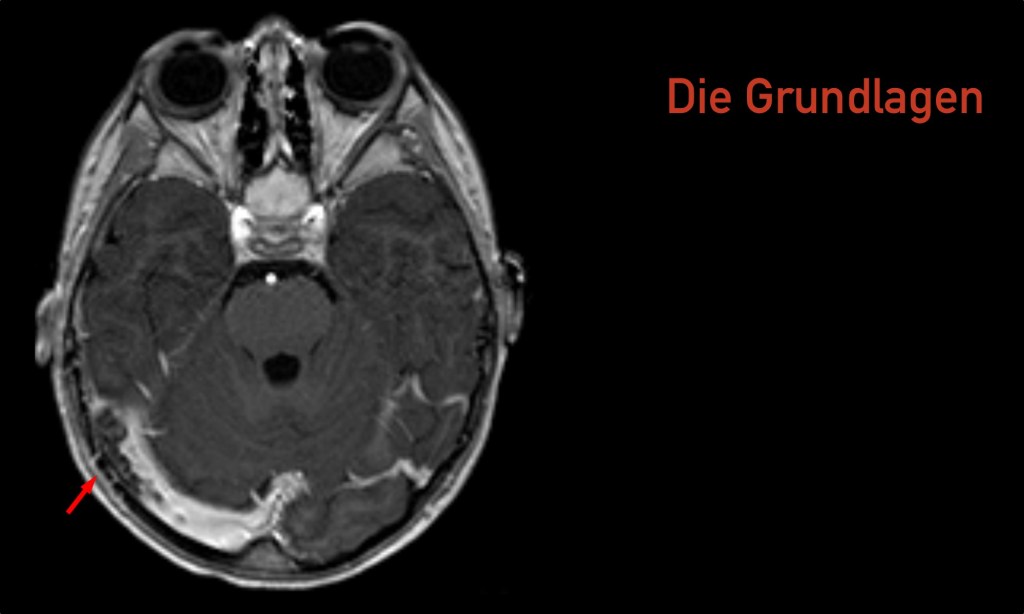

Vorwort Ja, wir sind keine Radiologen. Ja, in der heutigen Zeit, in der es immer mehr um medikolegale Konsequenzen unseres Tuns geht, sollten wir uns nicht überschätzen und selbst radiologische Befunde erheben ohne die formale Qualifikation dafür zu haben. Ja, auch fachärztliche radiologische Befunde sind oft falsch (oder mindestens diskutabel). Ja, ich erwarte von allen…